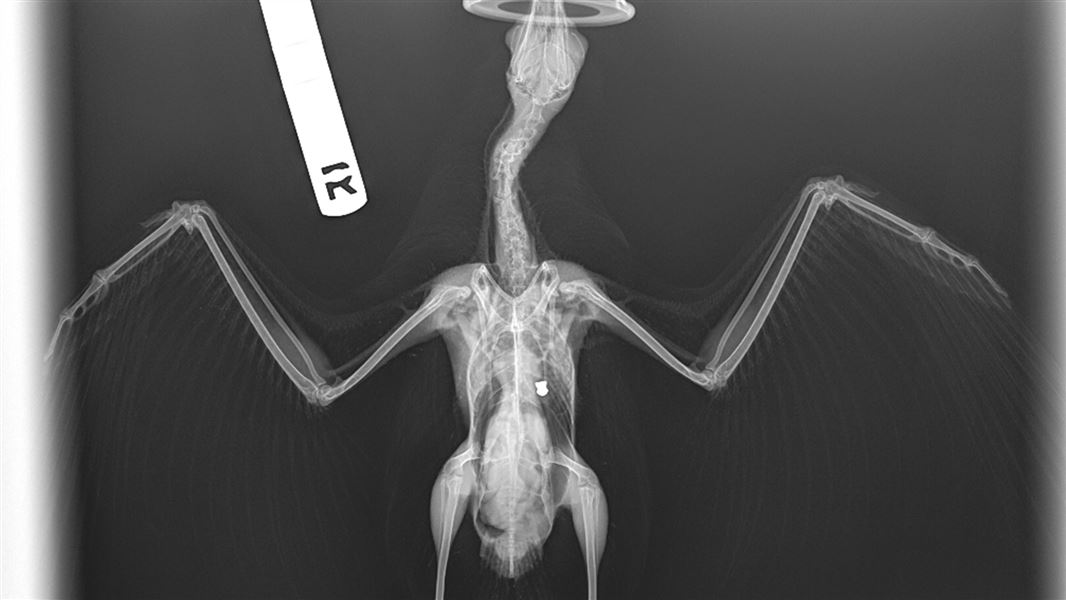

An xray of a red-billed gull with a BB gun pellet in its chest cavity

One red-billed gull was admitted to Dunedin Wildlife Hospital with an injured wing. Radiographs revealed a pellet or bullet in the body cavity. The injury was at least 2-3 weeks old given the skin had completely healed. The bird was in very poor condition and not able to use or feel the left wing, so he was sadly euthanised. During post-mortem the pellet was found to be embedded in the left lung. The gull also had aspergillosis infection, likely due to the stress and immunosuppression from the injury.